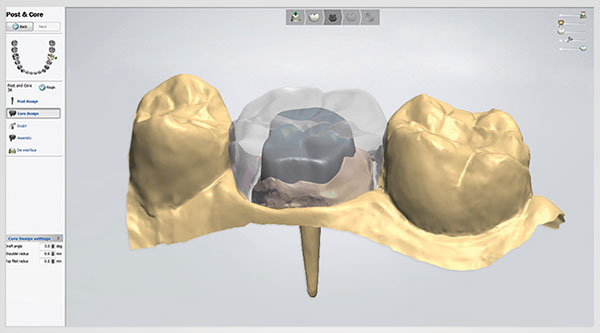

پرینت سه بعدی همچنین نقش مهمی در جراحی ایمپلنت دندان دارد. در واقع ممکن است یک مدل سه بعدی برای جایگزینی یک دندان ایجاد شود. در واقع، پرینت سه بعدی اجازه می دهد جایگزینی سریع تر و با دقت بیشتری نسبت به روش های سنتی برای دندان ایجاد شود. این نیز یک روش ساده و مقرون به صرفه می باشد. پرینت سه بعدی و ترمیم دندان ها در کنار یکدیگر آینده روشنی دارند.

- ۳shape، که به طور خاص برای مدل سازی سه بعدی دندانپزشکی ساخته شده است. بسته های مختلف براساس نیازهای شما در دسترس هستند. شما می توانید یک نسخه برای تاج دندان و پل، یکی برای اسکنها، و یا بسته هایی با تمام گزینه های مختلف تهیه کنید.

- DWOS Model Builder یک نرم افزار CAD ساخته شده توسط Dental Wings است. این نرم افزار سه بعدی شما را قادر به ایجاد مدل یا ایمپلنت با دقت خوب می کند.